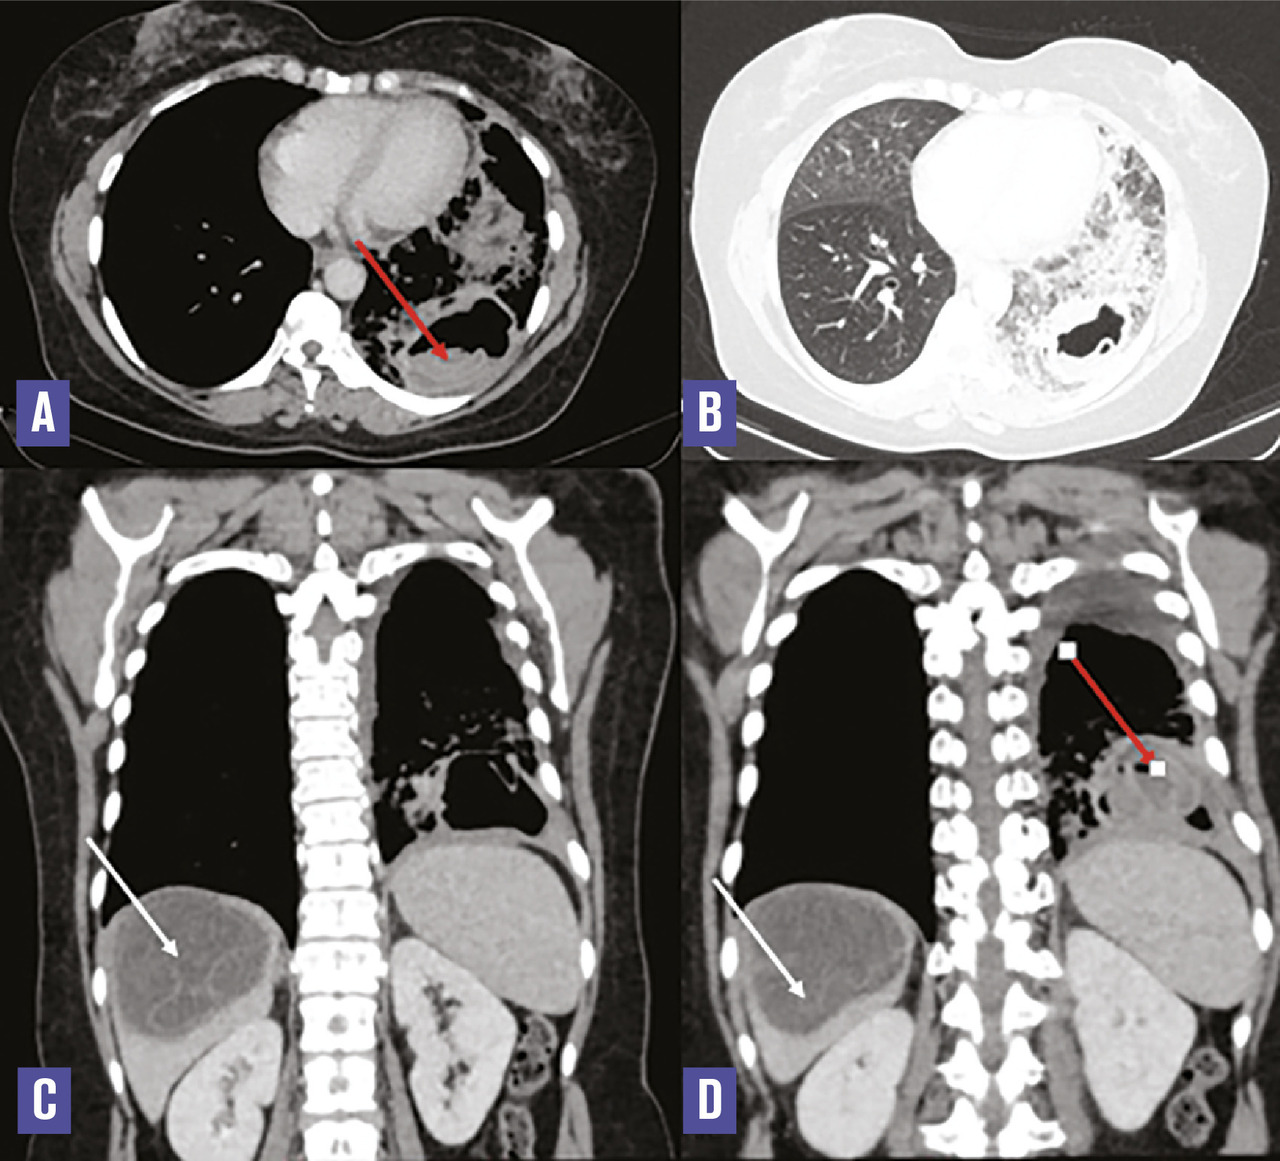

Cette femme de 40 ans consultait aux urgences pour des douleurs basi-thoraciques associées à une pesanteur de l’hypochondre droit. À l’examen clinique, elle était fébrile (38,5 °C) et polypnéique. Le bilan biologique montrait un syndrome inflammatoire. Sur la tomodensitométrie thoraco-abdominale (v. figure ) on notait deux masses pulmonaires du lobe inférieur gauche dont une était excavée, à paroi épaisse irrégulière et renfermant une membrane décollée et flottante (flèche rouge). Au niveau hépatique, il y avait une masse kystique à paroi fine du dôme, renfermant de multiples cloisons (flèche blanche). Après une chimiothérapie par albendazole, une résection chirurgicale des trois kystes était réalisée, l’étude histologique confirmant le diagnostic d’hydatidose.

La maladie hydatique est une infection parasitaire endémique due au développement chez l’homme de la forme larvaire d’Echinococcus granulosus.1 L’hydatidose multiviscérale, définie par la localisation simultanée de kystes hydatiques dans plus d’un organe, est peu fréquente. Elle pose des difficultés diagnostiques étant donné son polymorphisme d’où l’intérêt de réunir un faisceau d’arguments cliniques, sérologiques et radiologiques pour retenir le diagnostic. L’imagerie joue un rôle important dans le diagnostic positif, la recherche de complication et dans le bilan de surveillance. Le traitement est fondé essentiellement sur la chirurgie.2